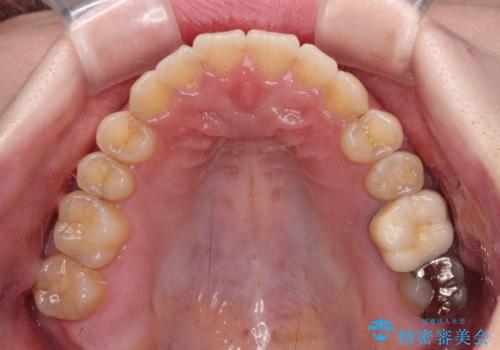

オープンバイトと前歯のデコボコをインビザライン矯正で解消

- 前歯の開咬を気にして来院された患者様です。

開咬の治療は、前歯を閉じるように動かすとともに、上下臼歯を圧下(骨内にめり込ませる)させることで進めて行きます。

インビザラインは臼歯の圧下を効果的に行えるため、インビザラインを用いて矯正治療を行うこととしました。